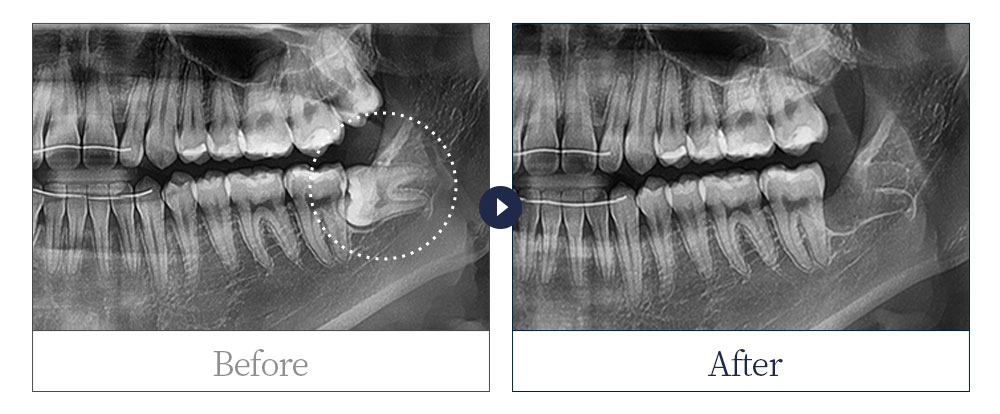

제목 20대 여 사랑니 발치 카테고리 사랑니발치

20대 여 사랑니 발치

치료 전: 20220323

치료 후: 20220330